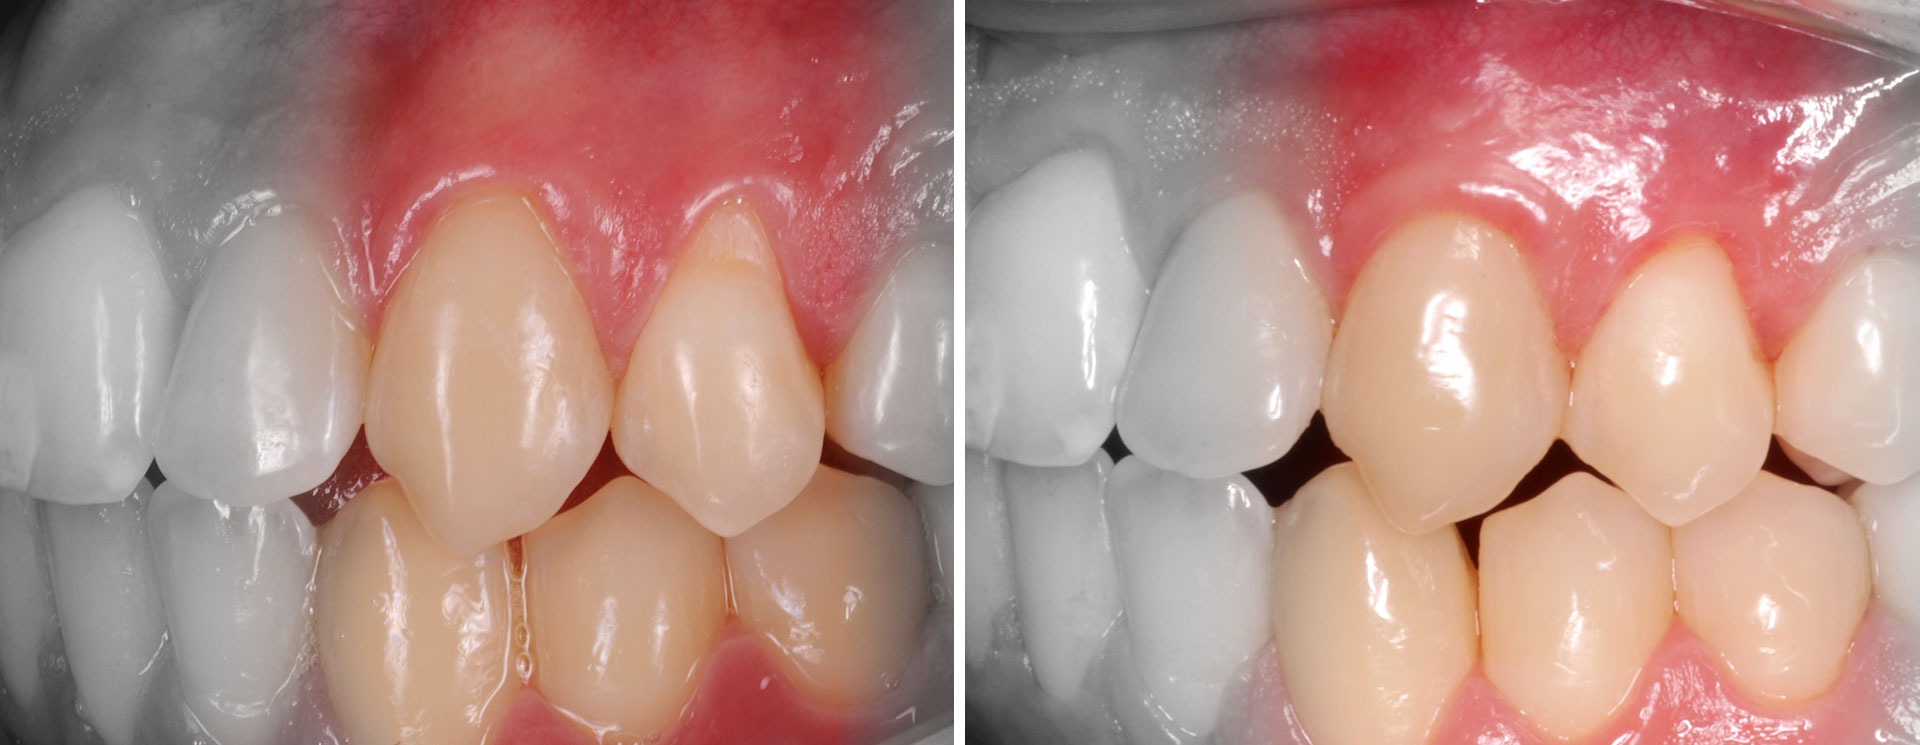

Gengivite

Para avaliação de suporte ósseo em redor dos dentes , o exame radiográfico é fundamental.